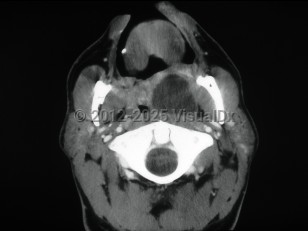

Peritonsillar abscess

This infection develops as a suppurative complication of acute tonsillitis or pharyngitis.

Patients present with a muffled voice, fever, sore throat, and dysphagia. There is deviation of the uvula to the unaffected side. Trismus and otalgia may be present. This infection usually affects young adults, but all ages can be affected. Older adults may have subtler symptoms. Laboratory findings include leukocytosis. Treatment consists of antibiotic therapy and surgical drainage.

Complications of this infection include airway obstruction or extension of the infection into contiguous spaces in the neck.